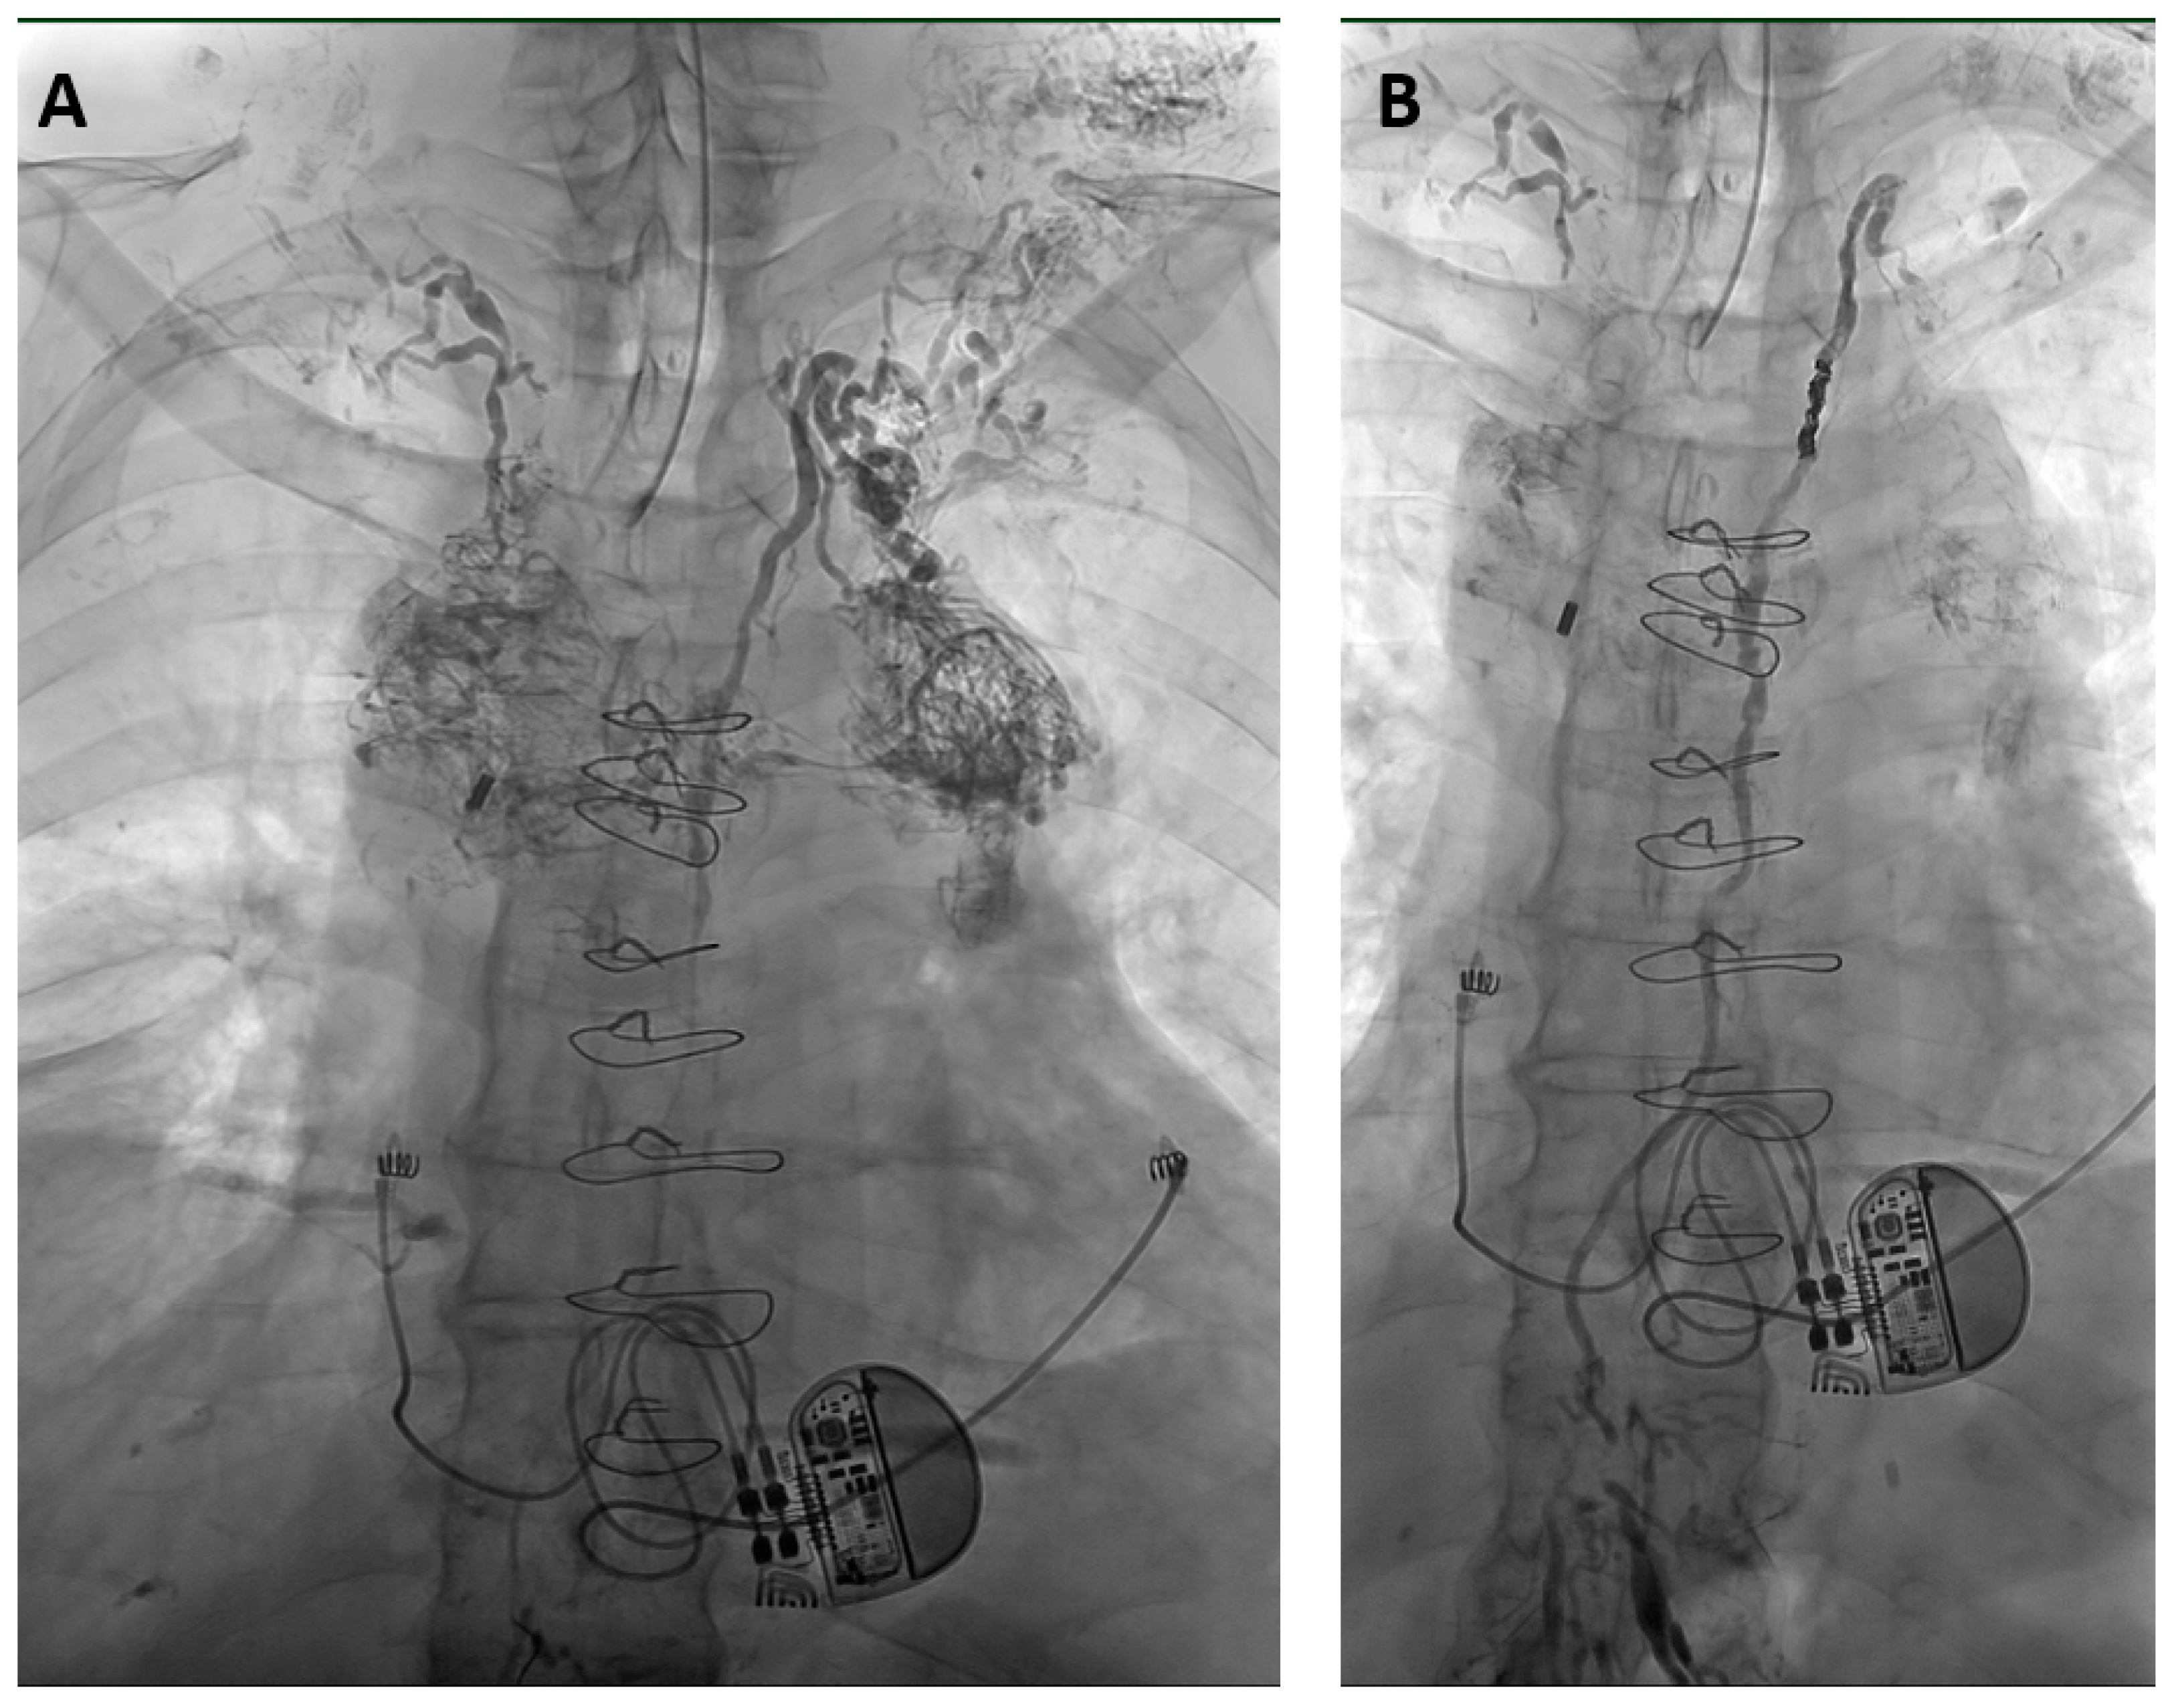

Figure 3.

65-year-old man with a non-traumatic bilateral chylothorax and chylopericardium. (A) X-ray lymphangiography shows chylous reflux from the upper thoracic part of the thoracic duct into dilated and tortuous lymphatic vessels in the mediastinum and cervical soft tissue. The right-sided lymphatic duct at the right venous angle can also be seen. (B) After thoracic duct embolization with micro-coils and a mixture of NBCA/iodized oil (ratio 1:3) leakage ceased within 2 days without clinical sequelae over a follow-up time of 4 years.